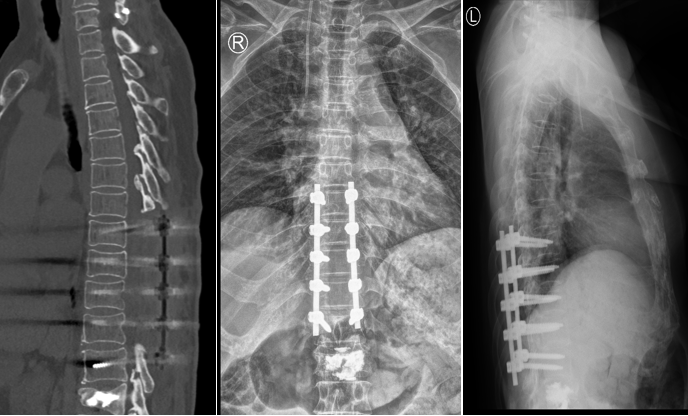

王阿姨近几年来时常感觉双下肢麻木,行走不稳,容易跌倒。王阿姨最近一次摔倒后,出现腰部剧痛、双下肢无力、行走困难的症状,家属立即带着王阿姨来到独墅湖医院骨科姜为民主任诊室就医。经查CT及MR显示:患者 L1压缩性骨折,T5-T12后纵韧带骨化。

L1骨折,合并胸椎管狭窄症

姜主任仔细查体后,确诊患者为“L1骨折,胸椎管狭窄症”。考虑到王阿姨年岁高,手术创伤性大,姜主任决定将治疗方案拆分成两个步骤,第一次手术行“胸椎椎板切除减压术+椎弓根钉内固定术+经皮椎体球囊后凸成形术”,第二次行“内镜下胸椎椎板切除减压术+黄韧带切除术”。

T8-T12椎板切除减压、L1骨水泥强化

胸椎管狭窄黄韧带骨化症是一类高致残性疾病,薄薄的神经如同松软的豆腐,任何一点损伤都可能导致不可逆的后果,切除骨化的黄韧带就好比在刀尖上表演舞蹈。姜主任将最新的UBE技术应用到王阿姨的手术治疗中,通过3个1cm的小切口在内镜下顺利从胸椎后方对T5-T7椎板完成了切除减压,并通过薄化技术一点一点切除骨化的黄韧带,用时153分钟顺利完成了“内镜下胸椎椎板切除减压术+黄韧带切除术”,术中出血60ml。术后,患者下肢麻木症状明显好转。在医院稍作休养后,即顺利康复出院。这次的UBE微创手术让王阿姨的印象尤为深刻,切实体会到了微创手术的神奇。